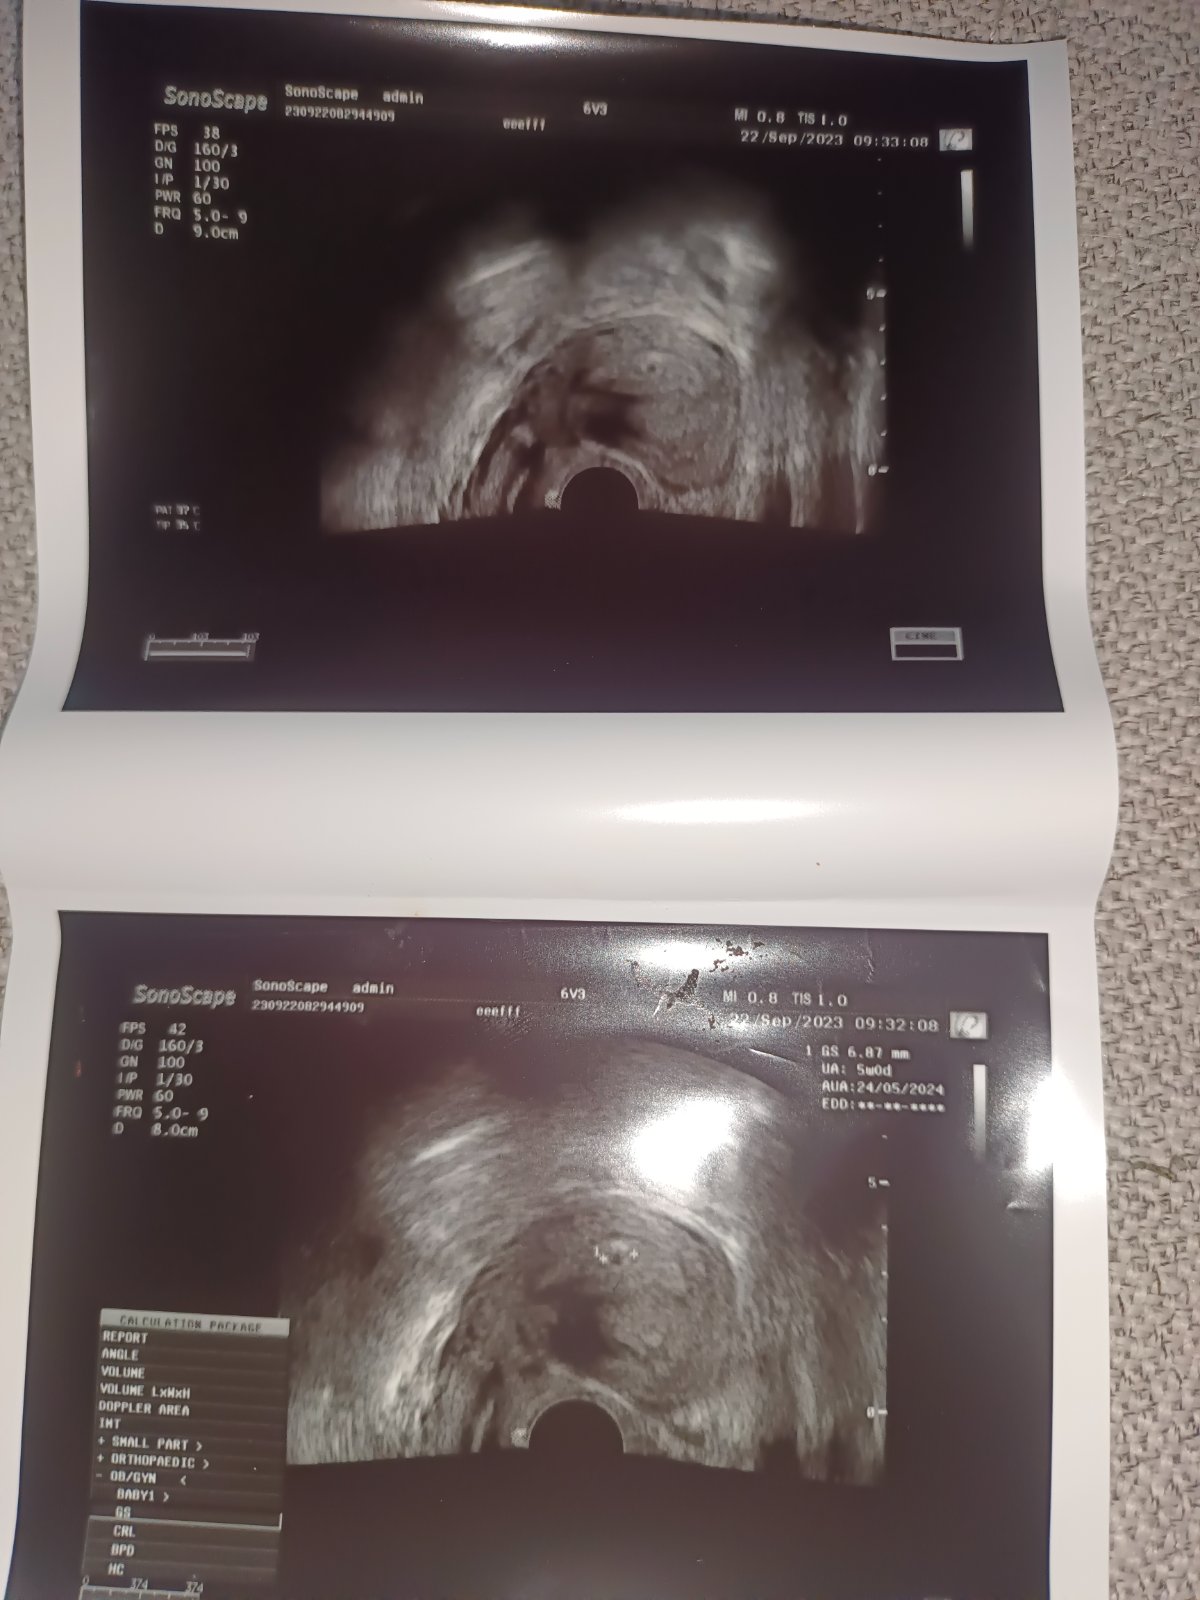

Změnila jsem pana doktora vše mi na uktrazvuku vysvětlit, dokonce jsem u sebe měla jen drobný a kartu, a říkal že nevadí že přinesu příště, dál mi dvě fotky zatím teda jenom gestační váček, dle MS bych měla být 6 týden dle ultrazvuku 5+0 nález odpovídá týdnu, takže se teď hodně šetřím, snažím se jíst zdravěji a moc se nenervovat a nepřepínat, za 3 týdnů jdu znovu, snad už na mě bude mávat malý obyvatel❤️❤️

@lusiana777 gestační váček 6,87mm je to v pohodě? Asi kdyby nebylo tak by doktor řekl něco že?😀